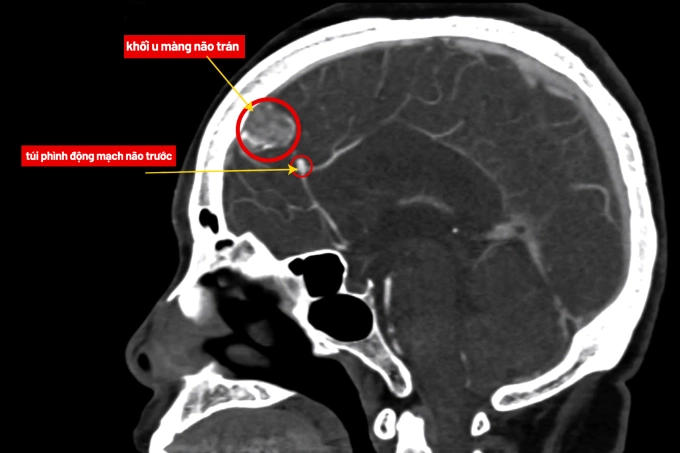

Ảnh chụp MRI khối u và túi phình mạch não của bà Hiền. Ảnh: Bệnh viện Đa khoa Tâm Anh

TS.BS Nguyễn Đức Anh, Trưởng khoa Ngoại Thần kinh Cột sống, Bệnh viện Đa khoa Tâm Anh Hà Nội, cho biết túi phình của bà Hiền có nguy cơ vỡ gây xuất huyết não. Trong khi đó, u màng não phát triển dễ chèn ép, tạo áp lực lên nhu mô não và hệ thần kinh.